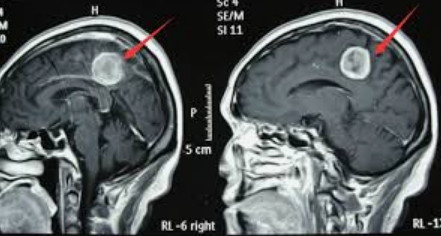

脑膜瘤怎么判断是良性还是恶性?多数时候,单凭脑膜瘤的症状还不能完全确认脑膜瘤的性质,通过CT、MRI等影像学检查,对于良、恶病现明显的一般可以分辨。